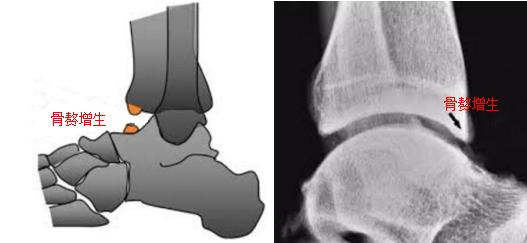

足球踝发生的原因众多,它是许多原因共同作用的结果。其一,大力踢球时,反复的跖屈(脚尖伸直)会造成踝关节前关节囊出现裂口或者反复被牵拉损伤,从而产生关节囊及韧带钙化。其二,反复用力跖屈时,有时会引起胫骨和距骨前面的挫伤;关节反复超常范围的活动致使胫骨和距骨和本身或关节软骨的异常撞击、挤压与磨损,时间长了在胫骨前侧会长出骨赘,距骨上也可能会长出骨赘,这些骨赘的形成,便引起了关节囊和骨以及骨与骨之间的撞击。其三,踝关节反复扭伤后的关节不稳定,也容易导致胫骨和距骨的磨损。